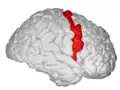

| Precentral gyrus | |

![]() Precentral gyrus a prominent gyrus of the frontal lobe | |

The precentral gyrus is a prominent gyrus on the surface of the posterior frontal lobe of the brain. It is the site of the primary motor cortex that in humans is cytoarchitecturally defined as Brodmann area 4.